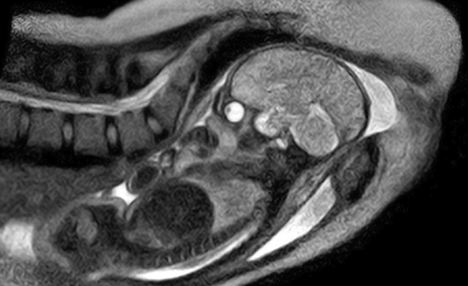

據英國《每日郵報》12月7日報道,德國柏林沙里特醫院近日實現了一項醫學突破,他們利用核磁共振掃描在全球首次獲得嬰兒降生過程的圖像。

這些圖像是在一個德國孕婦同意在核磁共振掃描儀里分娩后拍攝到的,它能夠為分娩過程提供一些有價值的新的認識,也可用于在將來拯救生命。

沙特林醫院的婦產科醫生恩斯特·拜茵德(音譯:Ernst Beinder)表示,該孕婦的整個分娩過程都很正常,機器拍下了孕婦子宮內的所有運動和整個分娩過程。“我們現在可以看到以前只能通過探針觀察到的全部細節,這些迷人的圖片再次證明了每個分娩都是一個小奇跡,”他說。

沙特林醫院研究團隊兩年前開始這項研究,本周終于取得成功。他們稱多名孕婦曾自愿參加這項實驗,另外還有5個孕婦的分娩過程將會被核磁共振掃描儀拍攝下來。醫院研究團隊為此還改進了通用的管狀核磁共振成像掃描儀,專門研制了一種特別的“開放式”掃描儀,以便為助產士和孕婦提供足夠的空間。

嬰兒出生過程的核磁共振成像圖片對于了解分娩并發癥至關重要,并能對大約15%需要接受剖腹產手術的孕婦的治療方案提供重要幫助。利用強大的磁體,核磁共振掃描儀能夠產生一個強大磁場,使無線電波探測到人體內的某些原子。研究人員則可用這些數據制作出患者身體的橫截面圖,提供軟組織和骨結構的細節。

核磁共振掃描儀被認為比X射線更安全,但因為它工作時總是發出嘈雜的嗡嗡聲,很多患者不喜歡這種設備。為了保護本周參加實驗的這位孕婦的健康,工作人員特意讓她戴上了耳套,當孕婦體內的羊膜囊破開后,因擔心嬰兒的聽力受損,掃描儀就被關閉了。